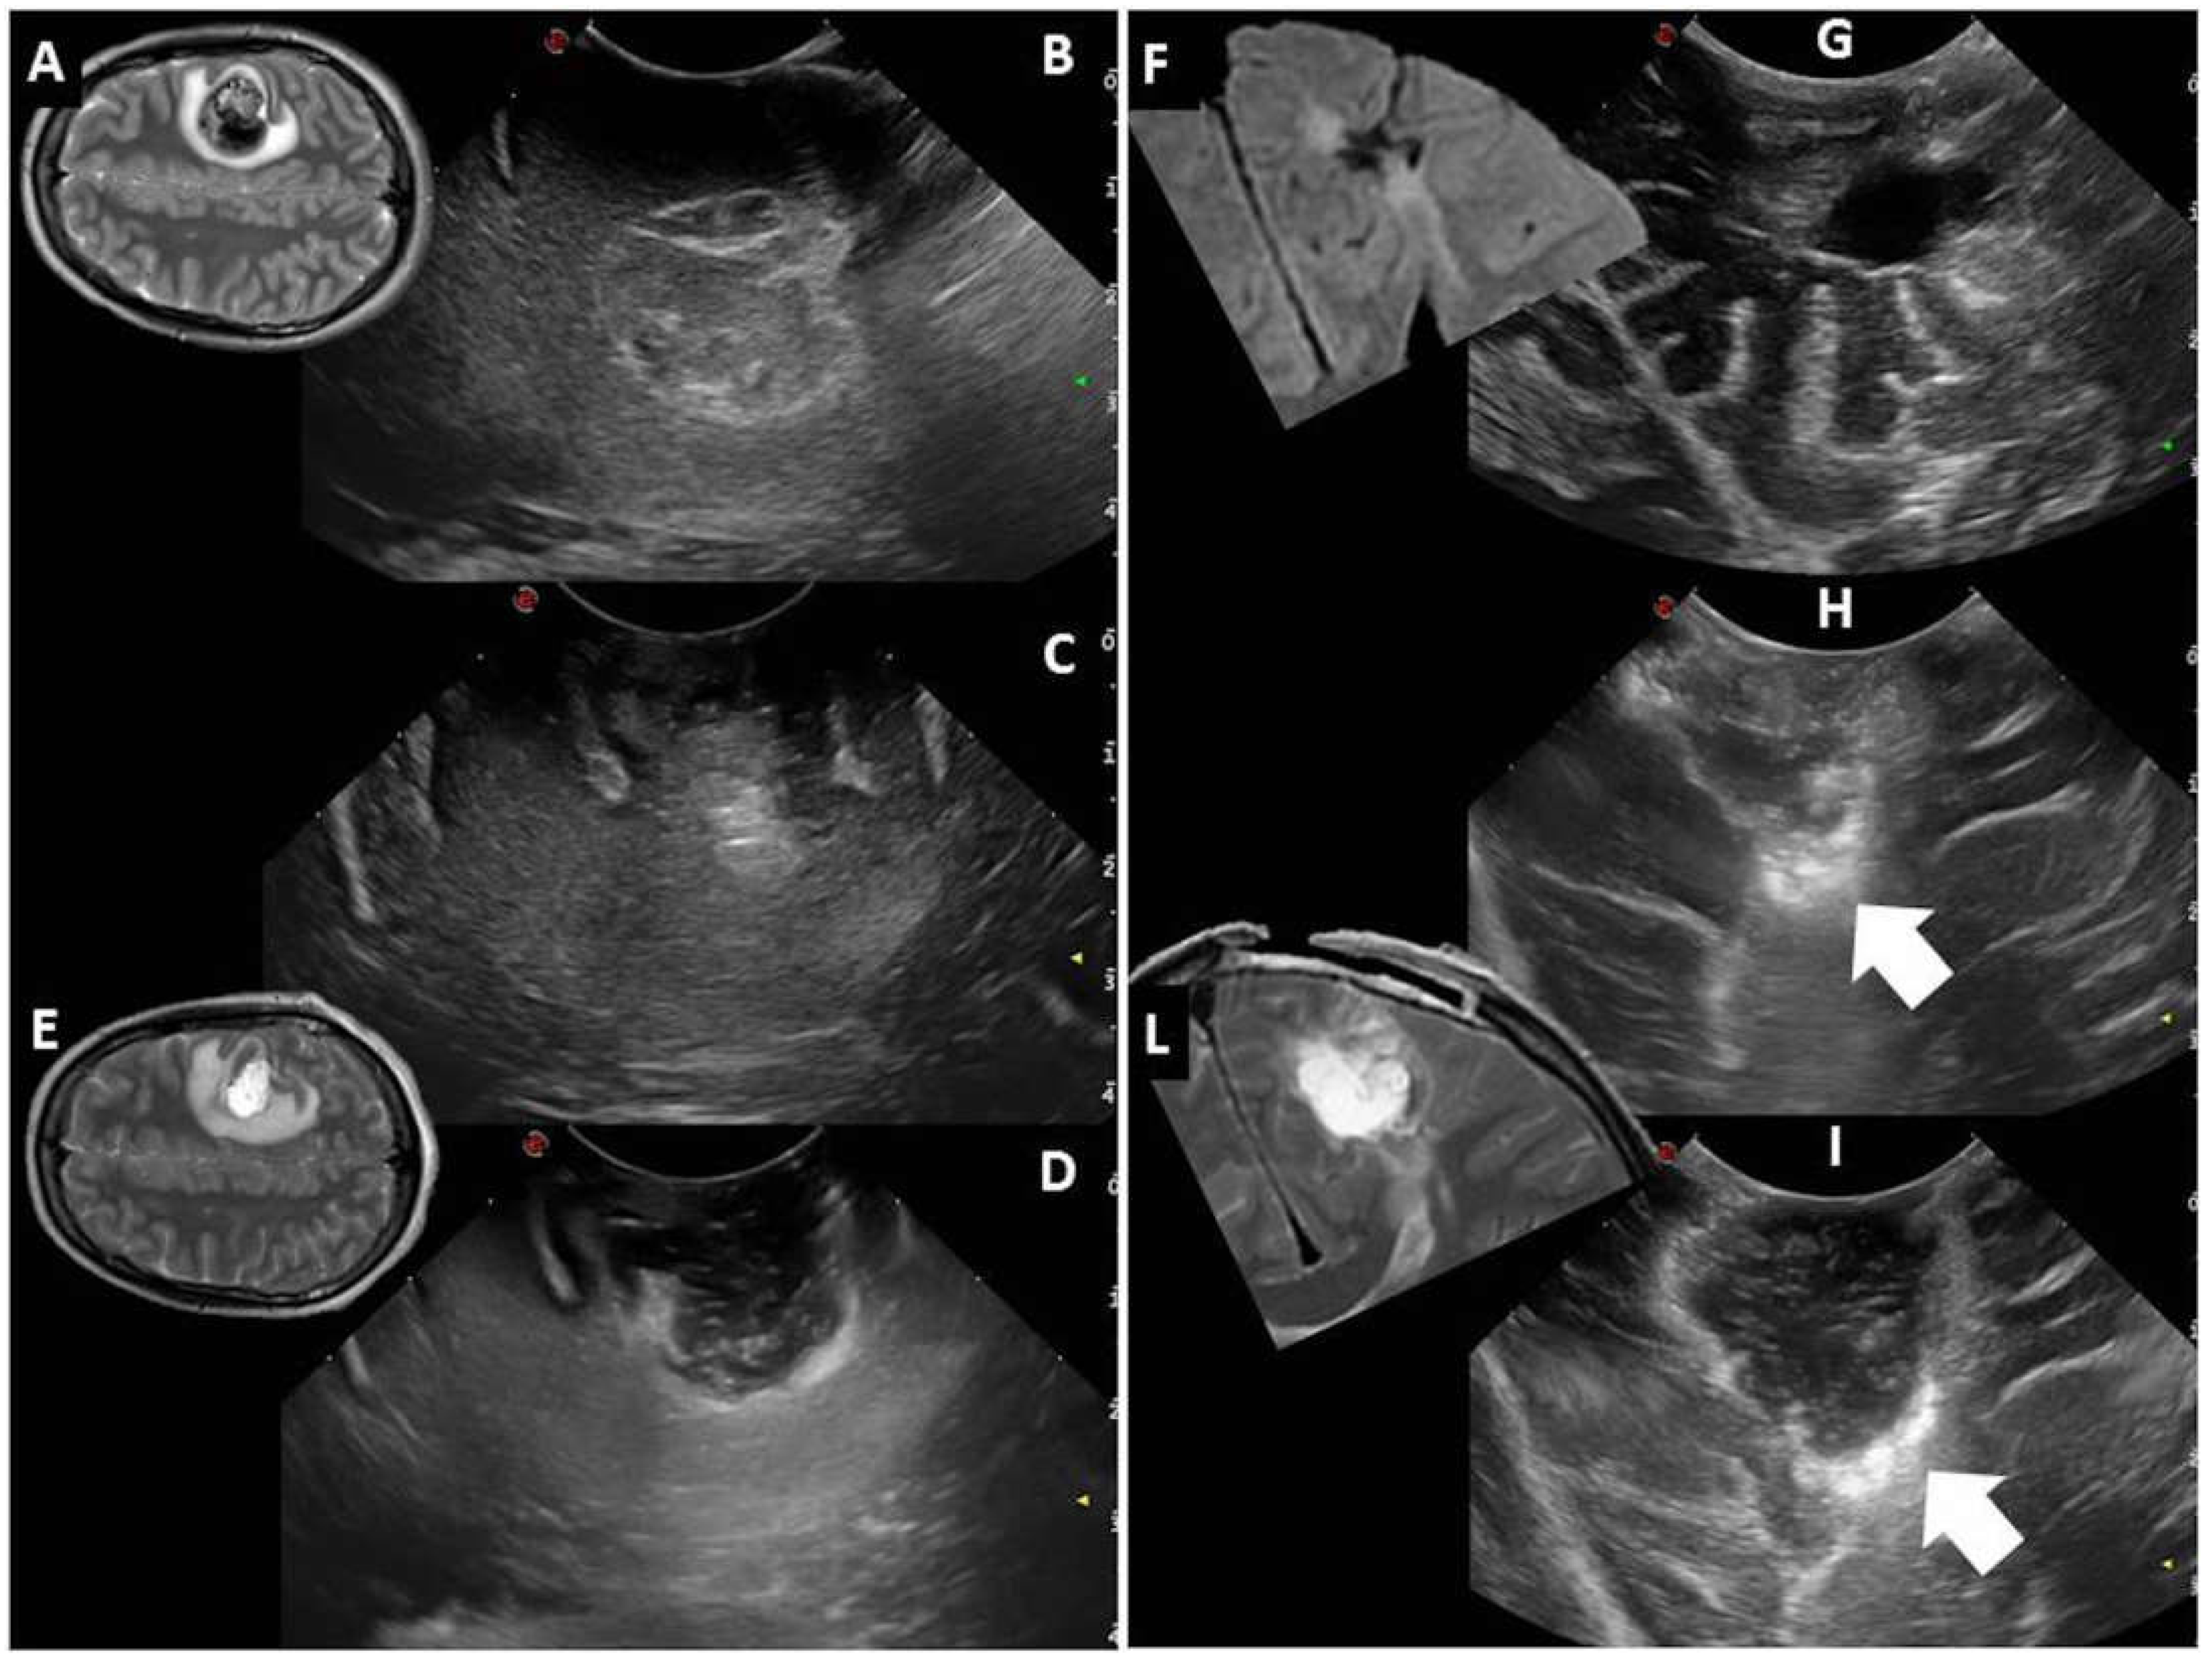

| Post-IOUS | ||

| EOR | Collapsed surgical cavity |

|

| EOR | Open ventricle |

| EOR | Artifacts |